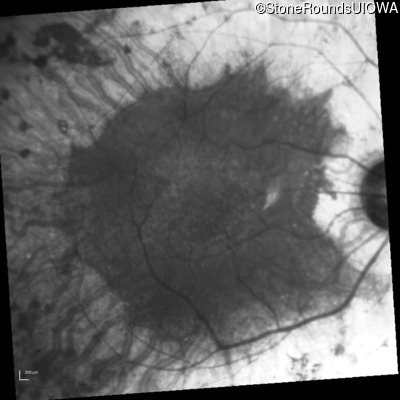

AR Retinitis Pigmentosa (IA1aiii)

Age at visit: 46 years

This 46 year old man has had poor vision in dim light since age 2.

Diagnosis & molecular findings

AR Retinitis Pigmentosa SLC24A1 Met252 del2ggaAT Leu1052 del2ctTC AR